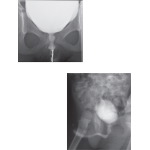

Male and Female Cystourethrograms

Male and Female Cystourethograms